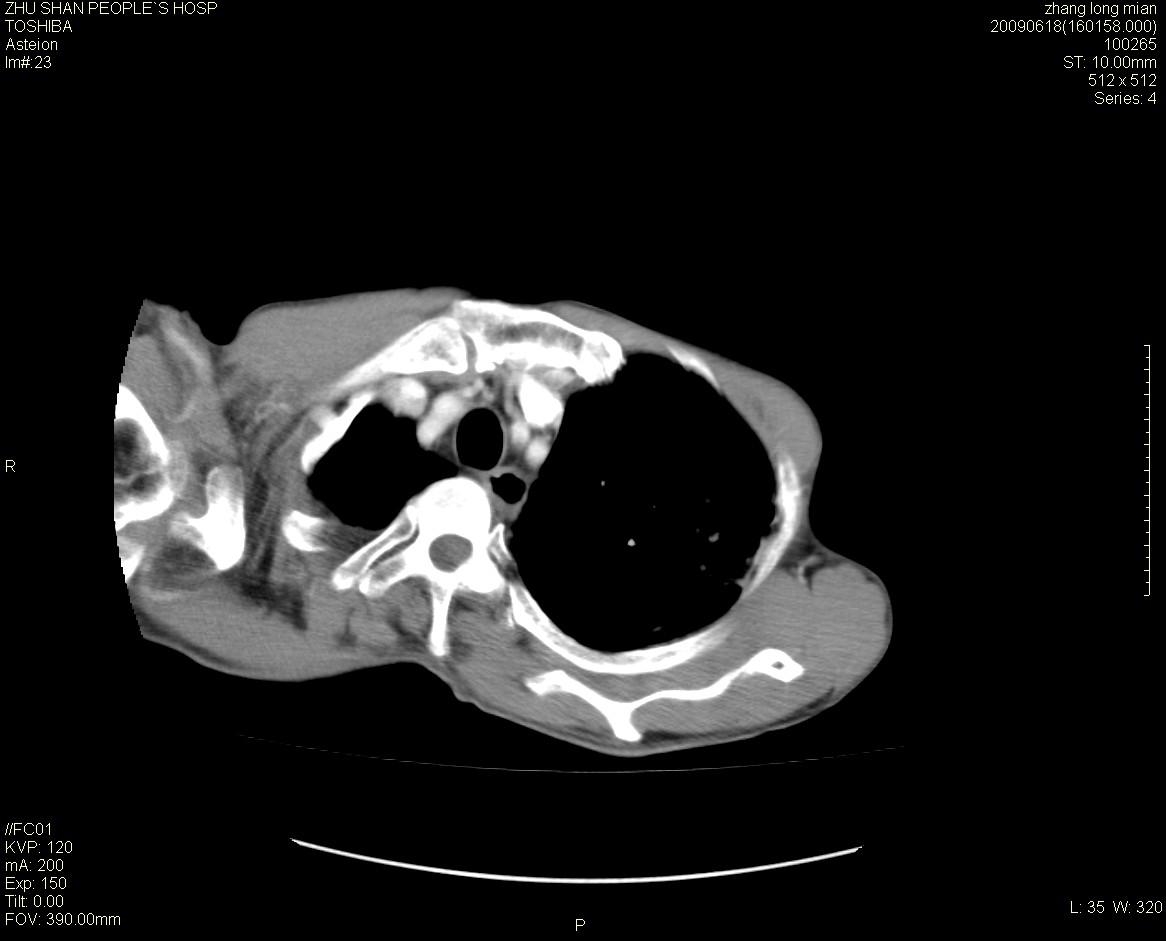

男性 65岁 胸片发现右下肺包块.诊断肺ca并纵隔转移没有问题吧!

两侧胸廓不对称,右侧呈塌陷改变,右肺萎缩。

这种患者扫描起来有难度。